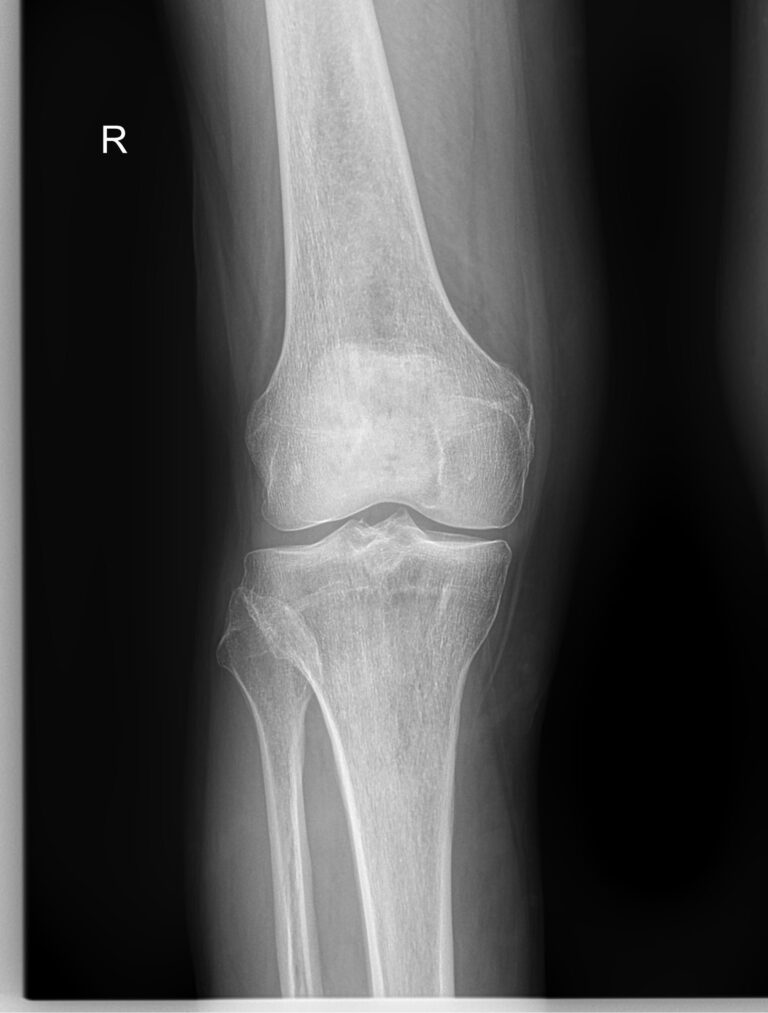

Рентген ― самый простой и быстрый метод диагностики поражения коленных суставов. Это неинвазивный и безболезненный , а также высокоинформативный способ увидеть внутреннее состояние колена. Современное рентгеновское оборудование использует минимально возможную дозу облучения. При этом на рентгенограмме отчетливо просматриваются части бедренной, малоберцовой и большеберцовой костей, надколенник, а также мягкие ткани вокруг них.

На рентгенограмме будут видны элементы сустава и патологические изменения в них:

• Суставная щель ― может быть расширена или сужена, причем неравномерно, иметь выпот, выросты, костные и хрящевые обломки;

• Соответствие друг другу суставных поверхностей ― естественное или вывих;

• Положение надколенника ― может быть неестественным;

• Состояние костной ткани: перелом, разрежение, уплотнение, размягчение, склерозирование;

• Мягкие ткани ― нормальные или отекшие, с инородными телами.